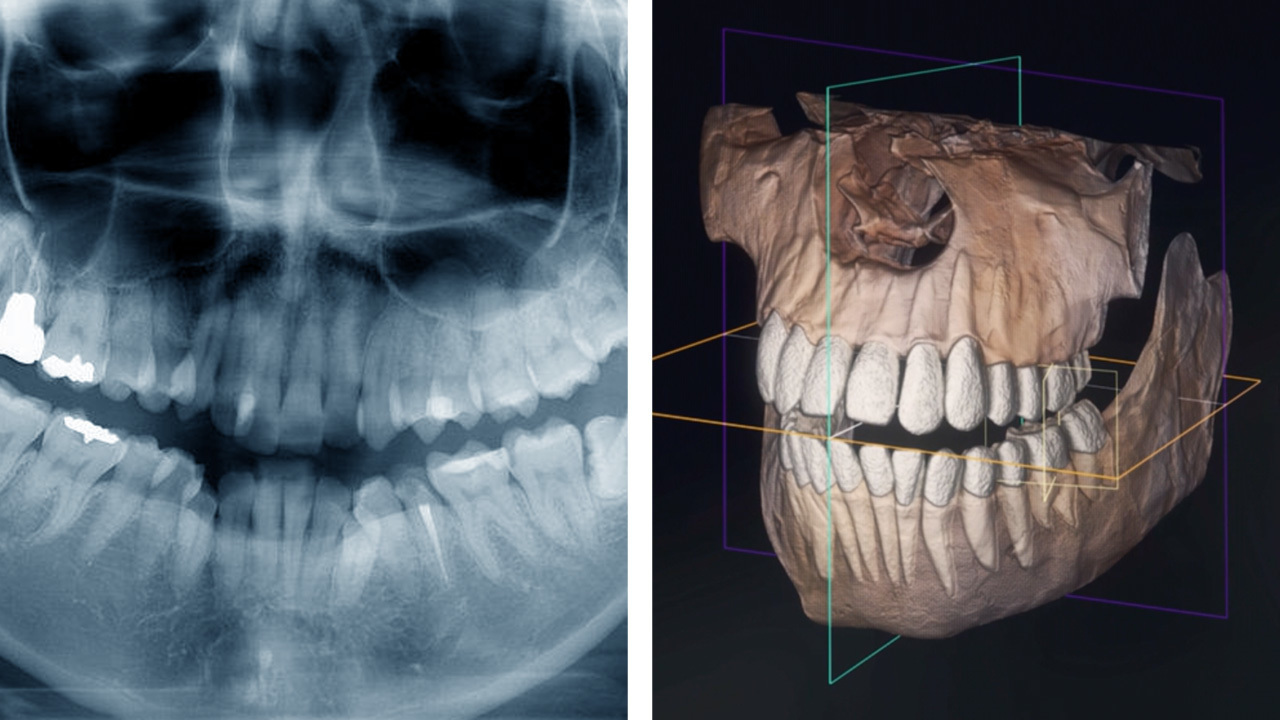

歯科用CTで検査してくれるか

院内に歯科用CTのない経験不足の歯科医師は、レントゲンの撮影だけで済ましてしまいがち。

CT撮影を行わずに治療を進めるケースが少なくありませんが、これが矯正治療に失敗する理由の一つ。

当院含め、矯正を専門に手がける経験豊富な歯科医師は、歯科用CTでの3次元診断を行います。

2次元レントゲンではわからない、骨の厚みや顎の幅、歯根の正確な長さ、顎関節の形状を三次元で見ながら診断することで、より安全で正確な治療計画を立てられるのです。